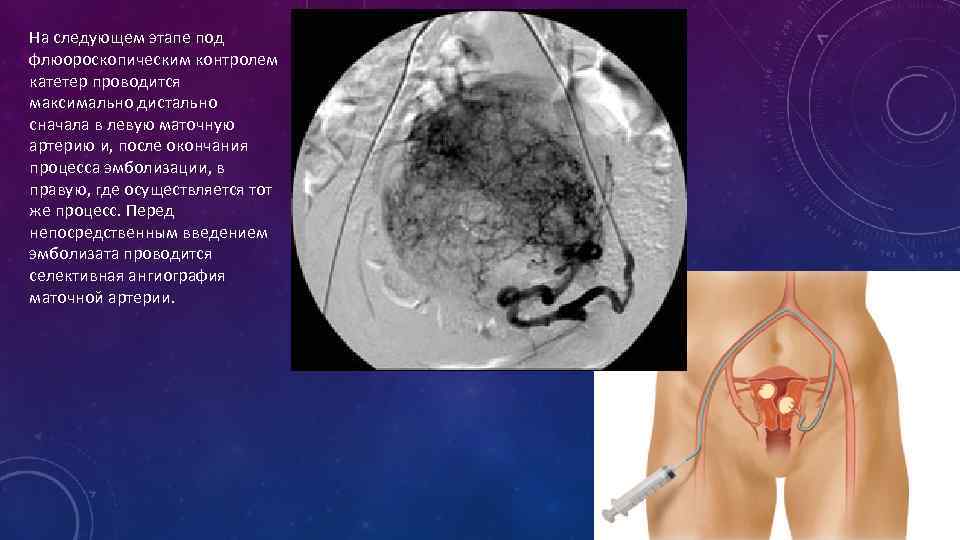

На следующем этапе под флюороскопическим контролем катетер проводится максимально дистально сначала в левую маточную артерию и, после окончания процесса эмболизации, в правую, где осуществляется тот же процесс. Перед непосредственным введением эмболизата проводится селективная ангиография маточной артерии.